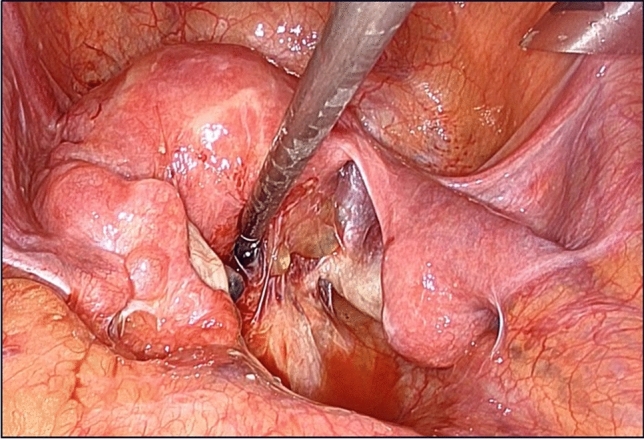

Results: The patient underwent Hartmann's procedure for generalized peritonitis resulting from perforation of the sigmoid colon. The abdominal cavity was significantly contaminated with fecal ascites, and postoperative pelvic adhesions were anticipated. Therefore, the rectal stump was lifted. The outcomes demonstrated that despite the presence of dense adhesions in the abdominal cavity, the rectal segment was promptly identified during the reversal of Hartmann's procedure. The procedure proceeded smoothly and was deemed satisfactory.